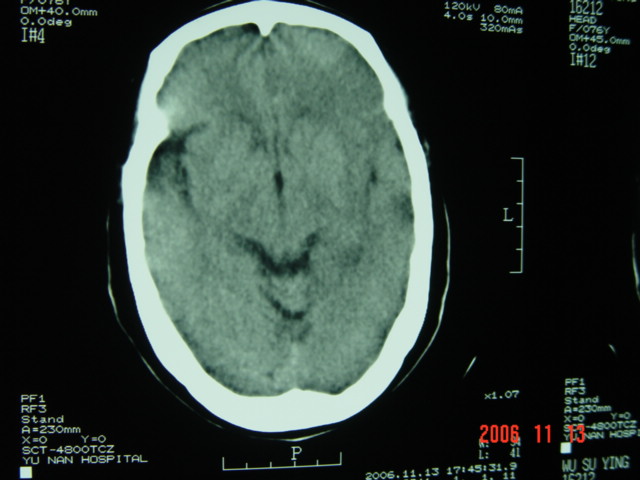

失语及右侧肢体无力3小时

左侧大脑半球与对侧相比较密度普遍密度降低,结合临床首先考虑是脑梗塞早期,必要时复查或mri。

左侧脑表面脑变窄,左外侧裂池受压变窄。

左侧大脑半球密度减低,左外侧裂消失。脑梗塞

左侧侧裂池消失,脑沟变浅.典型的一侧大脑半球缺血改变.可以诊断:左侧大面积脑梗塞.

左侧大脑半球密度普遍降低,脑沟池消失,考虑大面积梗塞

左侧大脑半球大片密度减低影,脑沟变浅,外侧裂变窄,中线结构无明显移位。左侧大面积脑梗塞,大脑中动脉堵塞所致,愈后不好呀!应早期溶栓啊。

左侧颞顶叶皮层与白质呈大片状低密度影,左侧脑室颞角,及侧裂池受压变小.中线居中.

典型的左侧大脑半球缺血性脑梗塞早期表现[左侧大脑半球皮质密度减低与脑白质密度一致(脑皮质征),左侧豆状核轮廓模糊,密度与脑白质一致(豆状核征),结合临床有失语及右侧肢体无力3小时]。